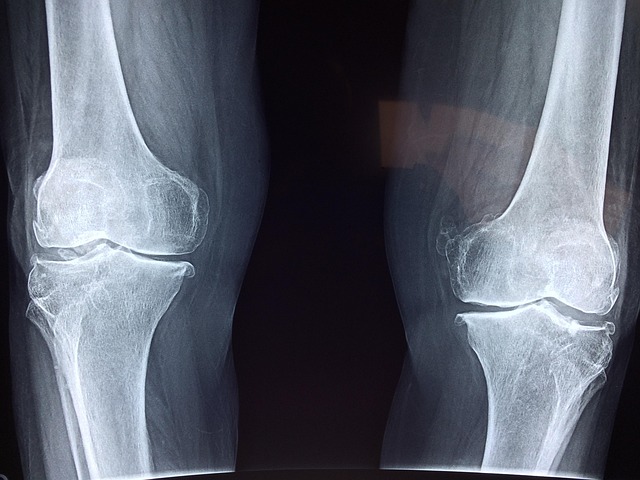

관절염, 비 오기 전에 아프다는 말... 사실일까?

이런 말, 한 번쯤 들어보셨죠? 단순한 느낌이 아니라 의학적으로도 근거가 있습니다. 실제로 기압, 습도, 온도 변화는 관절에 영향을 미쳐 통증을 악화시킬 수 있습니다.

| 퇴행성 관절염 | ▲▲▲ | 나이 많을수록 증상 심화, 무릎·허리 중심 |